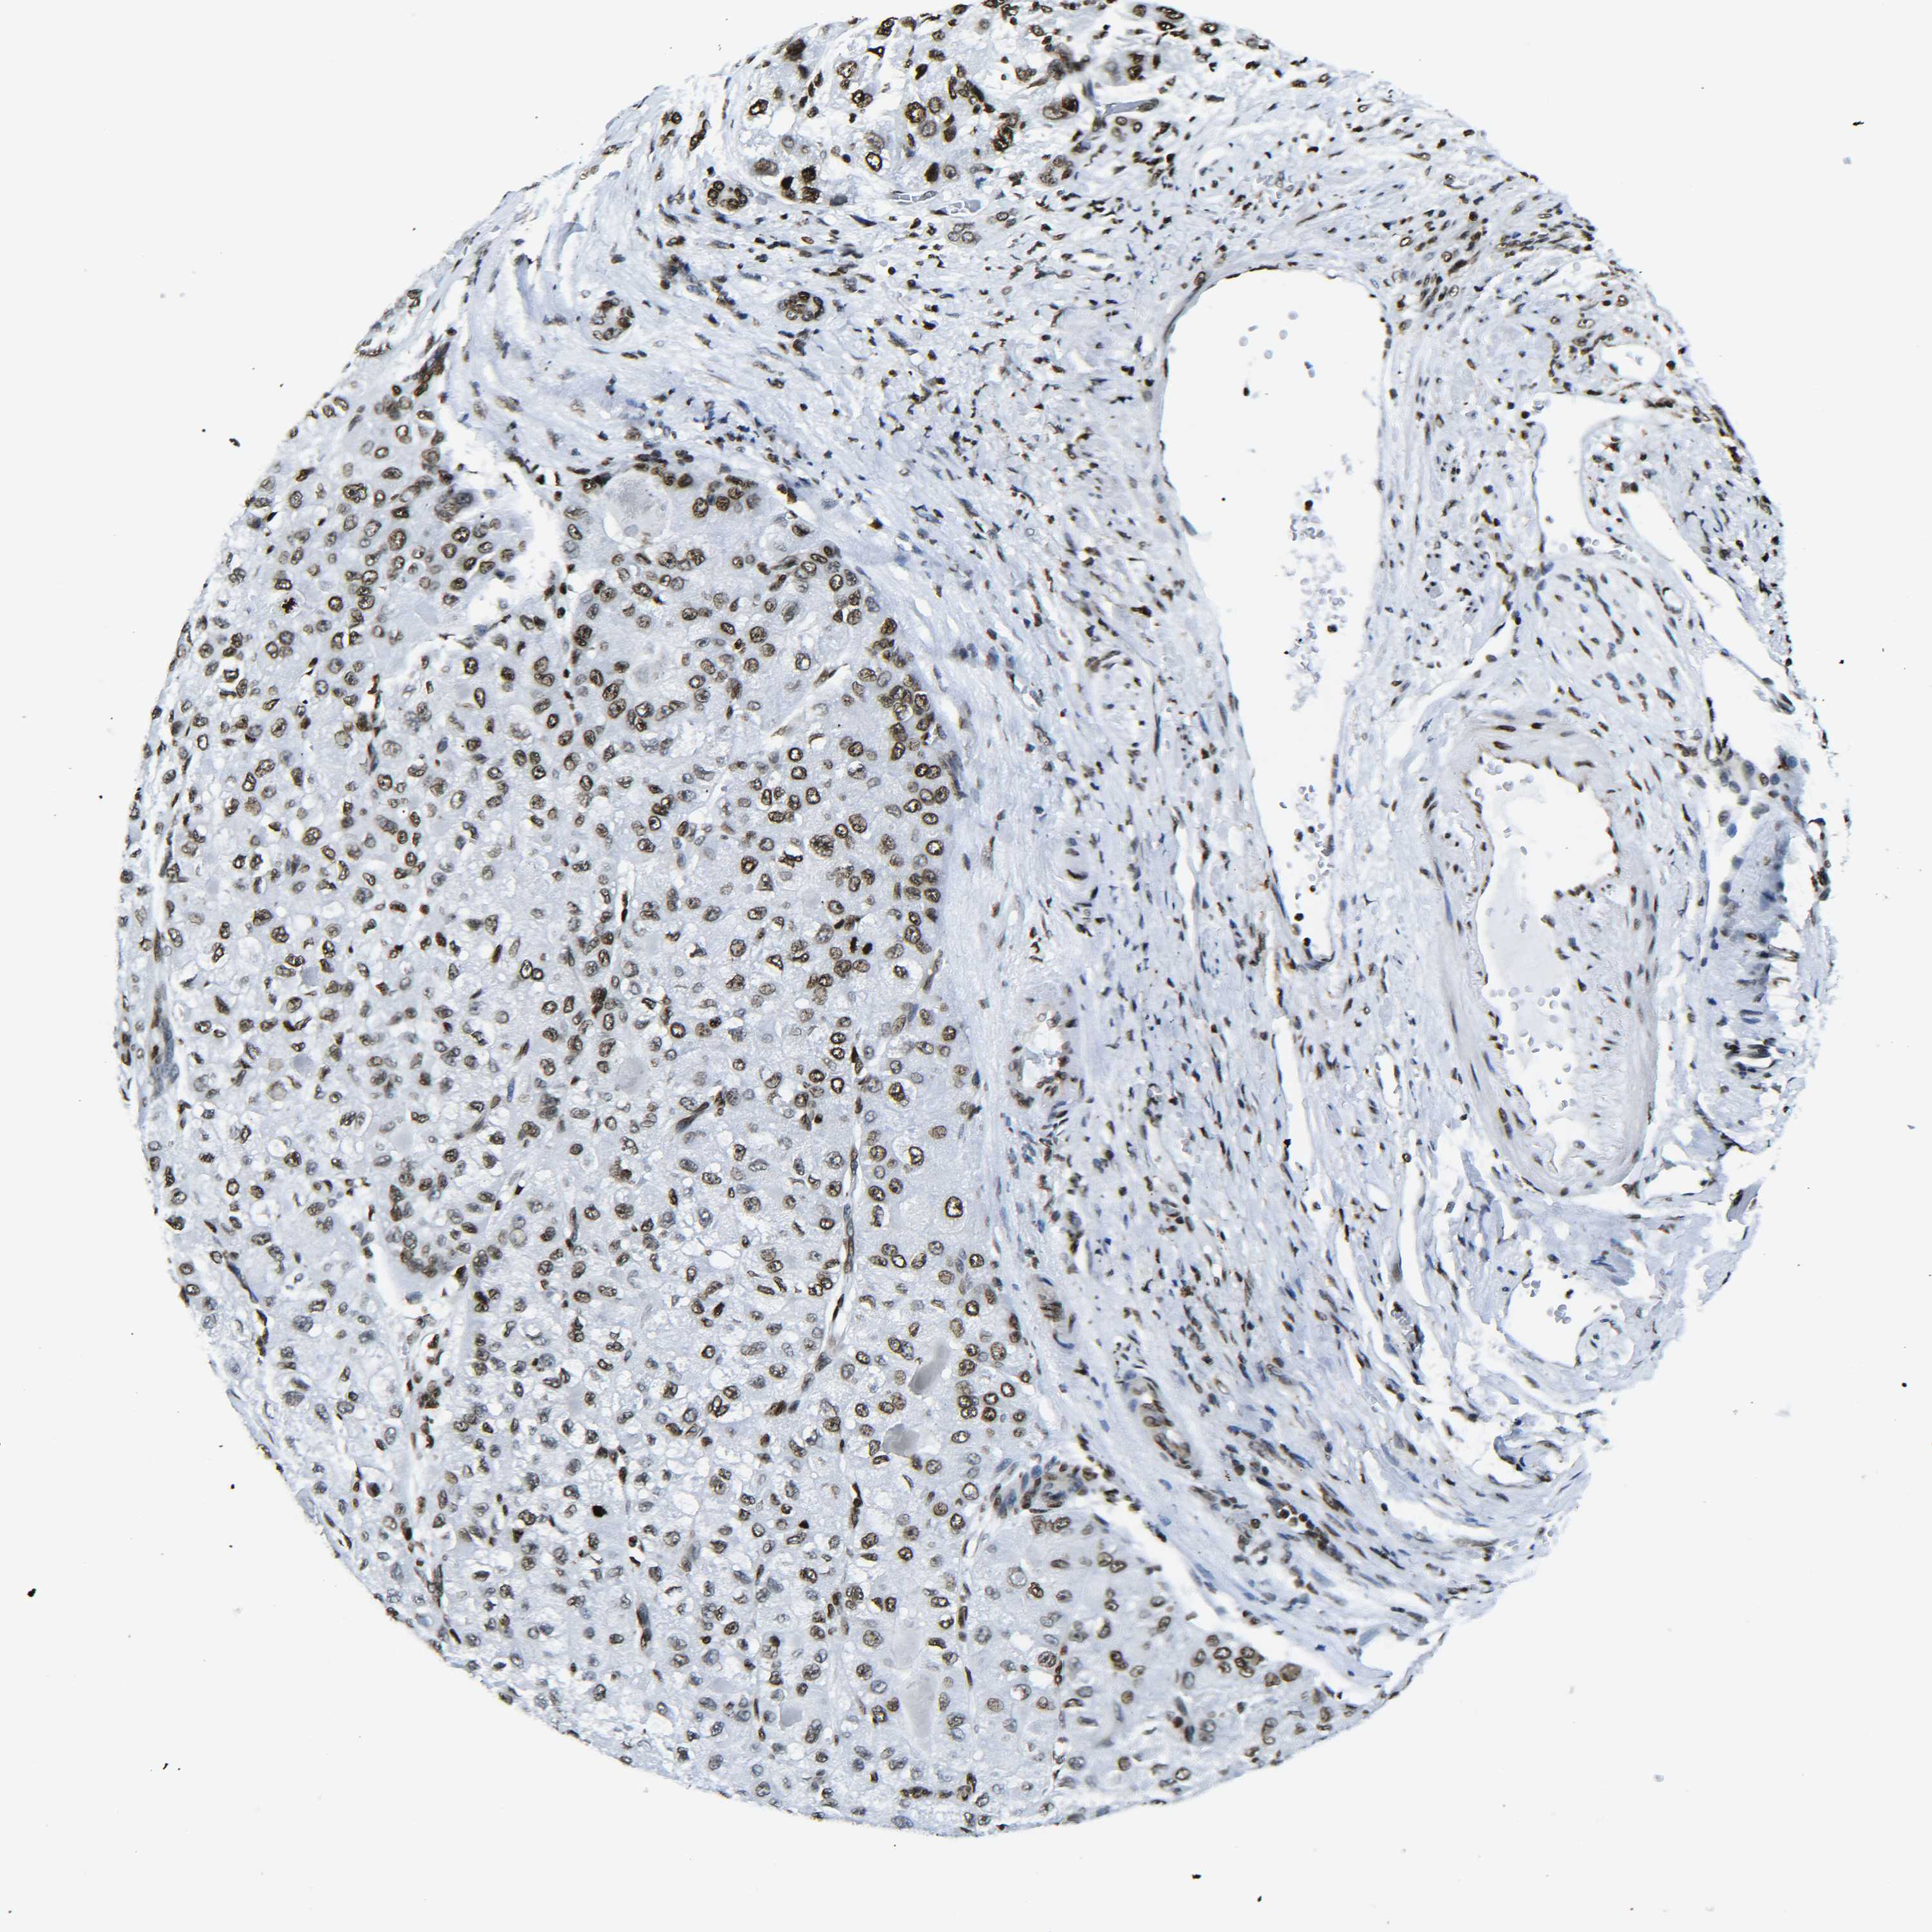

LIVER CANCER - Protein expressioni

A mouse-over function shows sample information and annotation data. Click on an image to view it in a full screen mode. Samples can be filtered based on level of antibody staining by selecting one or several of the following categories: high, medium, low and not detected. The assay and annotation is described here.

Note that samples used for immunohistochemistry by the Human Protein Atlas do not correspond to samples in the TCGA dataset.

Antibody stainingi

Antibody staining in the annotated cell types in the current human tissue is reported as not detected, low, medium, or high, based on conventional immunohistochemistry profiling in selected tissues. This score is based on the combination of the staining intensity and fraction of stained cells.

Each image is clickable and will lead to virtual microscopy that enables deeper exploration of all samples and also displays staining intensity scores, fraction scores and subcellular localization as well as patient and tissue information for each sample.

Antibody HPA041189

Antibody HPA051647

Antibody CAB012264

Staining

High

Medium

Low

Not detected

Intensity

Strong

Moderate

Weak

Negative

Quantity

>75%

75%-25%

<25%

None

Location

Nuclear

Cytoplasmic/membranous

Cytoplasmic/membranous,nuclear

Cholangiocarcinoma

Carcinoma, Hepatocellular, NOS